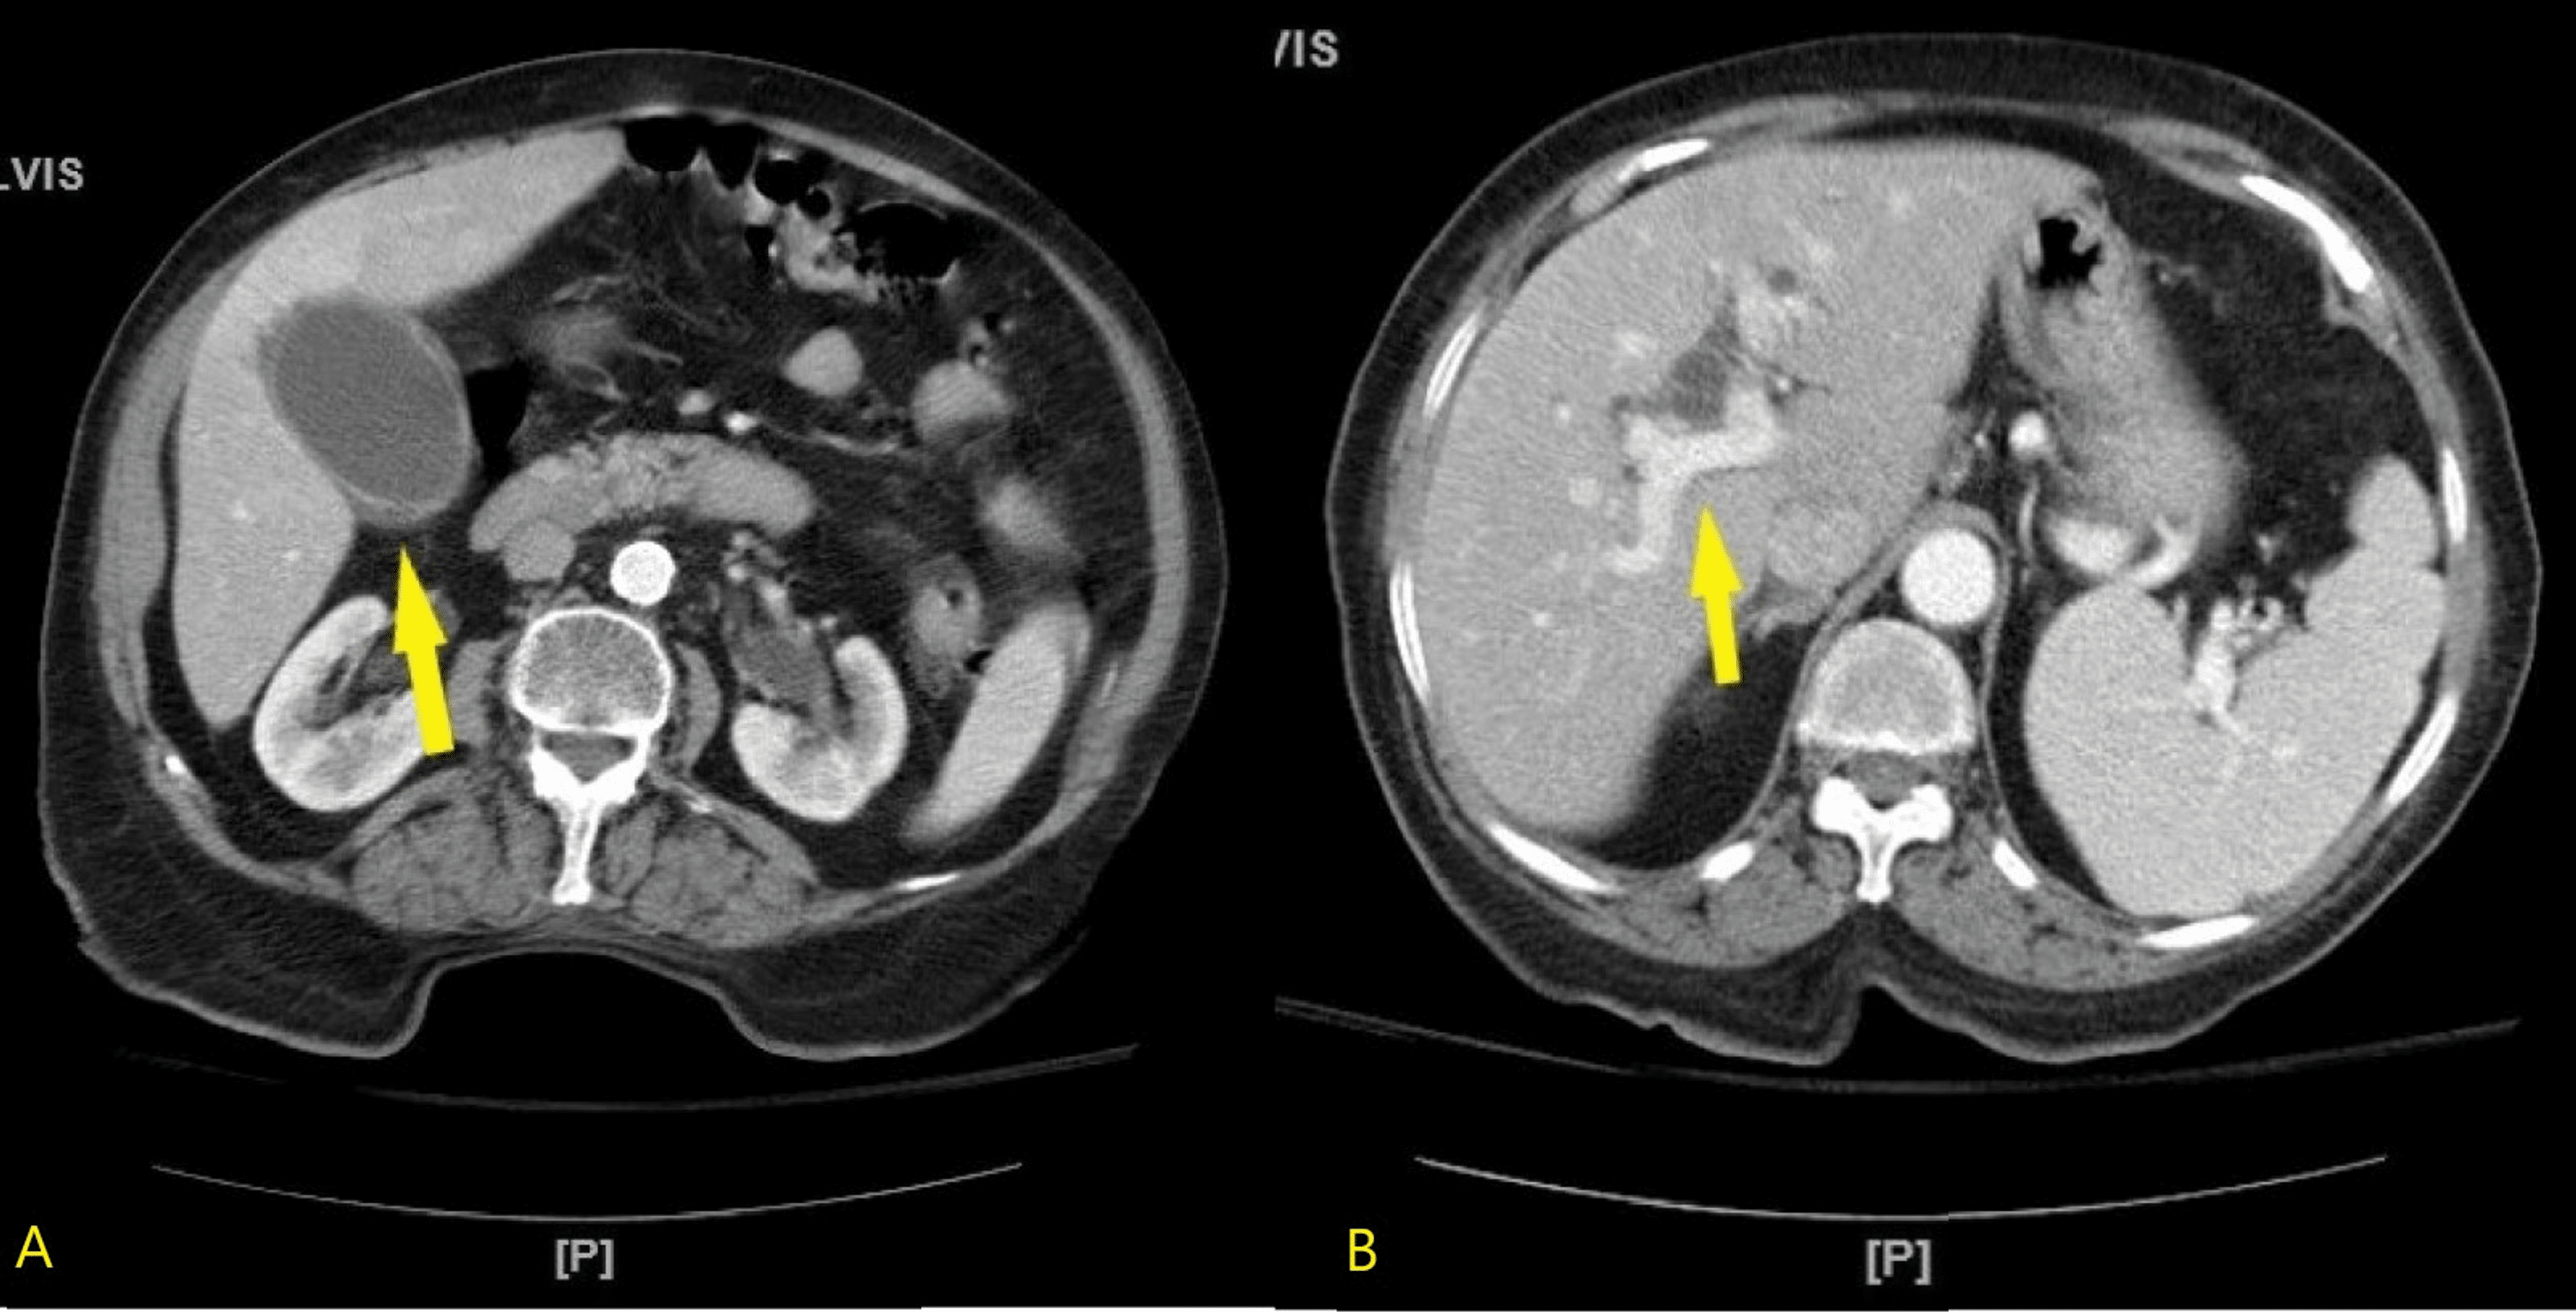

From radiologycases.my

Endoscopic removal of choledocholithiasis Radiology Cases Endoscopy For Cholelithiasis endoscopic retrograde cholangiopancreatography (ercp) is an invasive procedure used for the diagnosis and treatment of obstruction in the biliary system. gallstones (cholelithiasis) are hardened pieces of bile that form in your gallbladder or bile ducts. endoscopic retrograde cholangiopancreatography, or ercp, is a procedure to diagnose and treat problems in the liver, gallbladder, bile ducts, and pancreas. It. Endoscopy For Cholelithiasis.

Endoscopic removal of choledocholithiasis Radiology Cases Endoscopy For Cholelithiasis It is used to diagnose and. endoscopic retrograde cholangiopancreatography, or ercp, is a procedure to diagnose and treat problems in the liver, gallbladder, bile ducts, and pancreas. during endoscopic ultrasound (eus) your doctor passes a thin, flexible tube (endoscope) through your mouth and through. endoscopic retrograde cholangiopancreatography (ercp) is an invasive procedure used for the diagnosis and. Endoscopy For Cholelithiasis.